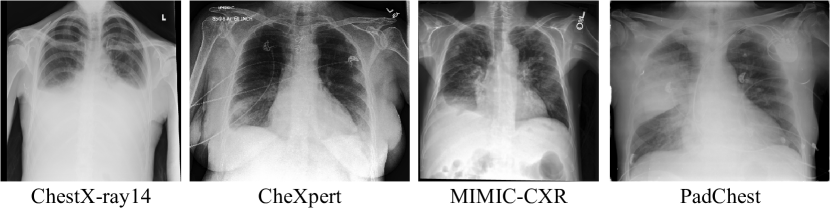

Three large datasets of chest radiographs are available to this date. ChestX-ray14 [20] from the National Institute of Health contains 112,120 frontal-view chest radiographs from 32,717 different patients labeled with 14 radiological findings. CheXpert [11] from the Stanford Hospital contains 224,316 frontal and lateral chest radiographs of 65,240 patients. MIMIC-CXR [13] from Massachusetts Institute of Technology presents 371,920 chest X-rays associated with 227,943 imaging studies from 65,079 patients. Both CheXpert and MIMIC-CXR are labeled with the same 13 findings. PadChest [2] 160,000 images obtained from 67,000 patients of San Juan Hospital in Spain. The radiographs are labeled with 174 different findings. Most labels from all four datasets are automatically extracted using natural language processing algorithms on the radiological reports.

We show the pixel intensity distribution of each dataset in Figure 2. We see a spike at low intensities (especially ) for every center. However, the distribution for higher intensities is somewhat different for every center, which might implicate in a decrease of the models’ predictive performance, except for CheXpert and MIMIC-CXR, which show similar distributions. Figure 3 shows the average radiograph of each dataset (computed using 10,000 random samples), in which we can see small differences in pixel intensity and that a common artifact appears on the top left corner of PadChest radiographs. Another difference that might implicate in domain shift is that PadChest labels are extracted from reports in Spanish, while the other three are extracted from reports in English.